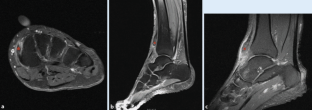

Abb. 1

Abb. 2

Abb. 3

Abb. 4